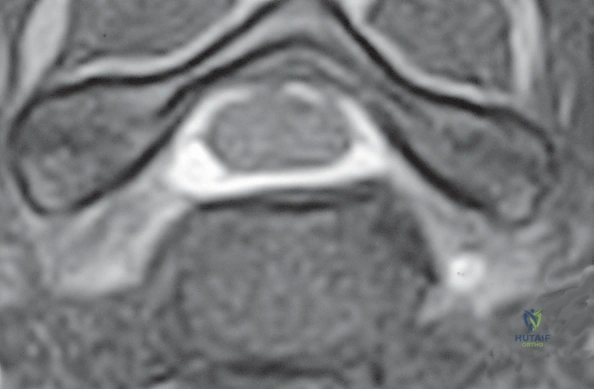

- التصوير بالرنين المغناطيسي (MRI): وهو الفحص الأهم لتحديد موقع الانزلاق الغضروفي بدقة ومدى انضغاط الأعصاب.

الخطوة 5: تخفيف الضغط العصبي (Decompression)

هذه هي المرحلة الأهم والأكثر حساسية. يقوم الجراح بإزالة أي نتوءات عظمية (Osteophytes) أو أجزاء من الغضروف الممزق التي تضغط على الأعصاب الشوكية أو الحبل الشوكي، مما يعيد للقناة الشوكية اتساعها الطبيعي.